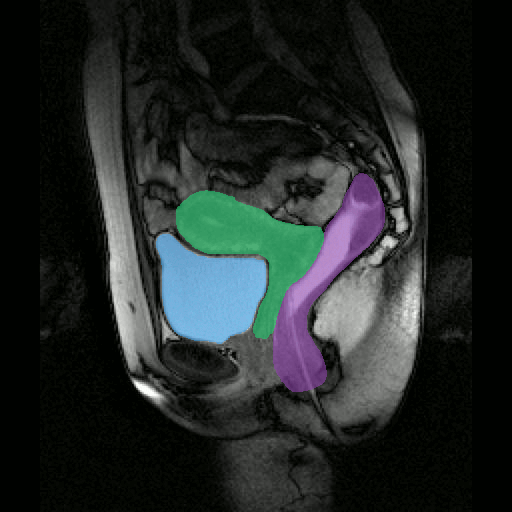

Semi-automatic segmentation of epicardial muscle and fat tissue on a cardiac cine MRI sequence.